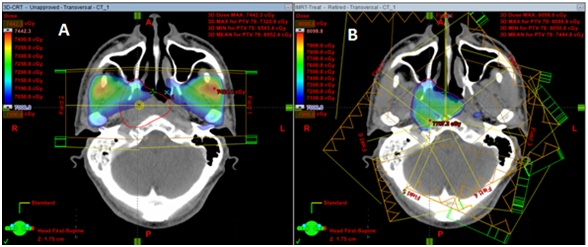

Xạ trị điều biến liều (IMRT) là một phương pháp xạ trị hiện đại được sử dụng để điều trị ung thư. Phương pháp này sử dụng tia X để tiêu diệt tế bào ung thư trong cơ thể. Tuy nhiên, điểm khác biệt của IMRT so với các phương pháp xạ trị truyền thống là khả năng điều chỉnh liều xạ tại từng vùng cụ thể trong khối u ung thư. Điều này giúp giảm tổn thương cho các cơ quan và mô xung quanh, đồng thời tăng hiệu quả điều trị.

Phương pháp này được thực hiện bởi các chuyên gia y tế, bao gồm các bác sĩ chuyên khoa ung thư và kỹ thuật viên xạ trị.Quá trình xạ trị điều biến liều bắt đầu bằng việc định vị chính xác vị trí của khối u bằng cách sử dụng các kỹ thuật hình ảnh như CT scan, MRI hay PET scan.

Sau đó, các chuyên gia y tế sẽ lên kế hoạch xạ trị, tính toán liều lượng tia X hoặc tia gamma cần thiết để tiêu diệt tế bào ung thư mà không gây tổn thương đến các tế bào khỏe mạnh xung quanh.Khi bệnh nhân bắt đầu quá trình xạ trị, họ sẽ được đặt trong một máy xạ trị đặc biệt, được điều khiển bởi kỹ thuật viên xạ trị. Máy sẽ phát ra các tia X hoặc tia gamma theo kế hoạch đã được tính toán trước đó, và tia sẽ được tập trung vào vị trí của khối u.